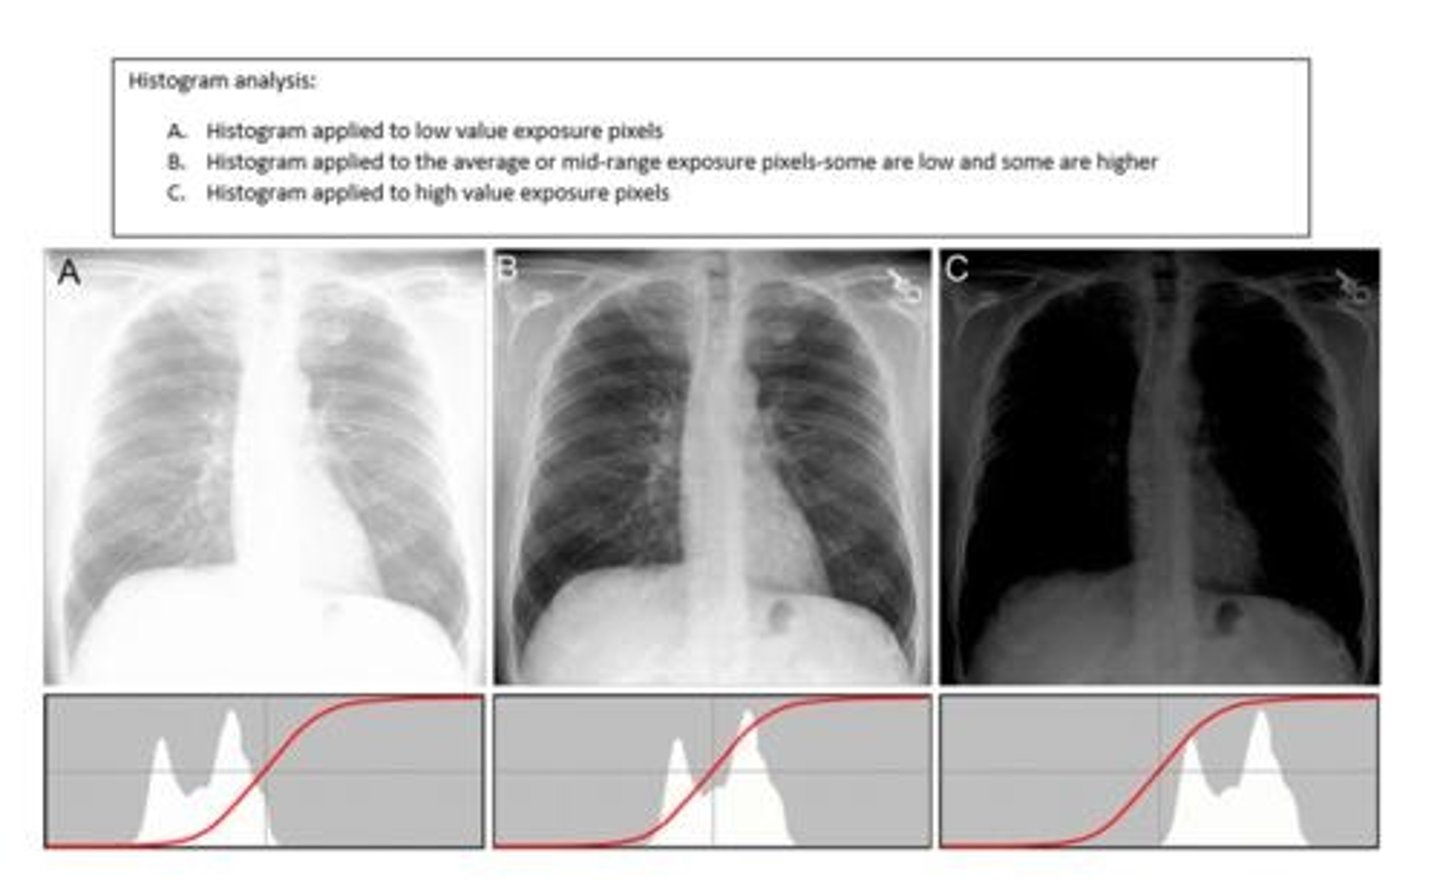

What is histogram analysis?

A histogram of the image taken is generated and then compared to an ideal histogram based off of the LUT for that view

Occurs before edge detecting and rescaling

Line on a histogram that follows the change of densities on an image. Brightness is represented by length from left to right and contrast is represented by steepness. Curve is adjusted to fit ideal contrast during rescaling.